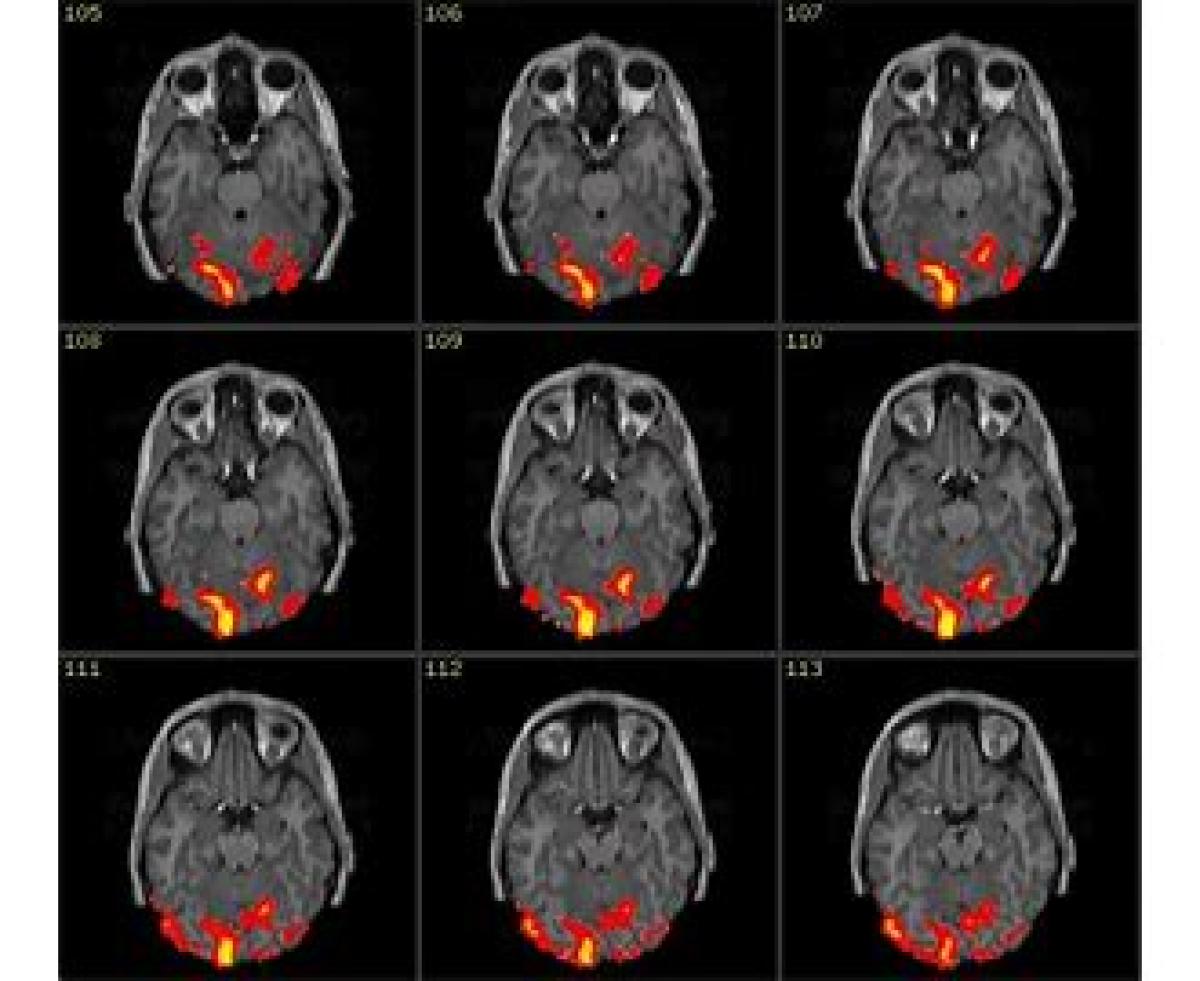

تصویرسازی تشدید مغناطیسی کارکردی، نام نوعی روش تصویربرداری در MRI است.

در این روش تصاویری متناوب از مغز در حال فعالیت و سپس در حال استراحت گرفته می‌شود و از یکدیگر بطور دیجیتالی (بکمک نرم‌افزارهایی همانند FSL) تفریق می‌گردند، که حاصل این پردازش عملکرد مغزی در اثر تغییرات جریان خونی در مغز را از لحاظ فیزیولوژیکی نشان میدهد.